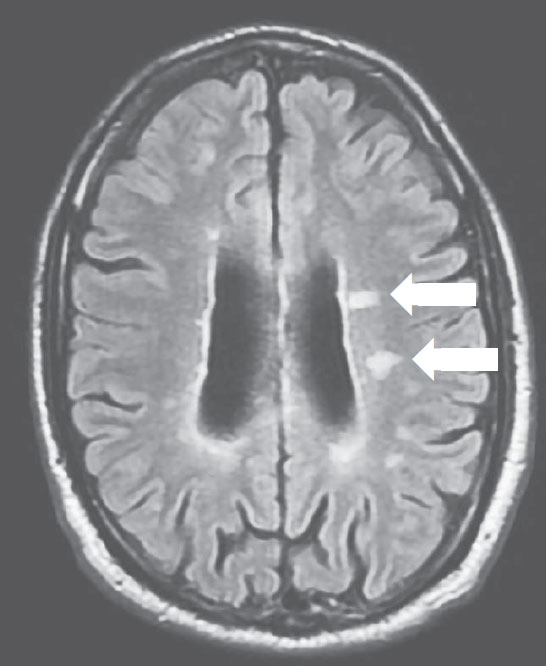

Оньека (имя героини и некоторые обстоятельства ее жизни изменены в целях защиты личных данных) меняется в лице, когда я показываю ей снимки магнитно-резонансной томографии, МРТ (рис. 1.1, 1.2).

РИСУНОК 1.1. ГОЛОВНОЙ МОЗГ ОНЬЕКИ, СНИМОК МРТ В РЕЖИМЕ T2-FLAIR, АКСИАЛЬНАЯ ПРОЕКЦИЯ. ОЧАГИ РАССЕЯННОГО СКЛЕРОЗА – НЕБОЛЬШИЕ БЕЛЫЕ ОБЛАСТИ, ОТМЕЧЕННЫЕ СТРЕЛКАМИ

Магнитно-резонансная томография дает возможность диагностировать РС и отслеживать его течение, позволяя прижизненно видеть очаги поражения (видимые области повреждения нервной ткани) в живом организме. Очаги при РС выглядят яркими пятнами на Т2-взвешенных изображениях, а при стойкой утрате нервных волокон – темными («черные дыры») на Т1-взвешенных изображениях. Активный очаг заболевания вызывает временное нарушение функций гематоэнцефалического барьера (барьера между кровеносной и центральной нервной системами), и вводимый перед исследованием гадолиний-содержащий контраст проникает в очаг, «подсвечивая» его на снимке. В результате таких повреждений головной мозг частично атрофируется (уменьшается в размерах) примерно на 0,5–1,35 % в год [3]. Для мониторинга РС проводятся регулярные осмотры и периодический МРТ-сканинг, поскольку новые очаги часто появляются бессимптомно.